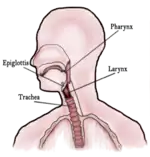

Го́рло[1][2][3] — часть шеи впереди позвоночного столба.

Верхней границей является подъязычная кость, нижней — рукоятка грудины и ключица. Термин «горло» является общеупотребительным, но не анатомическим. Он отсутствует в списке новейшей анатомической терминологии 1997 года[4]. Устаревшее слово означавшее горло — Жерло[5]. Через горло проходят многочисленные жизненно важные органы и системы:

- сонные артерии

- блуждающий и другие нервы

- пищевод

- трахея

- гортань

- глоточные мышцы и мышцы шеи